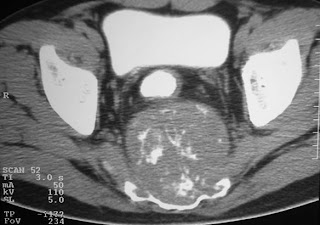

A 9-year-old male presented with mass on back since he was 4 year old. Local doctor have did operation but mass have growth again. We can see scar incision on back mass. Recently, he developed leg weekness now he cant walk.